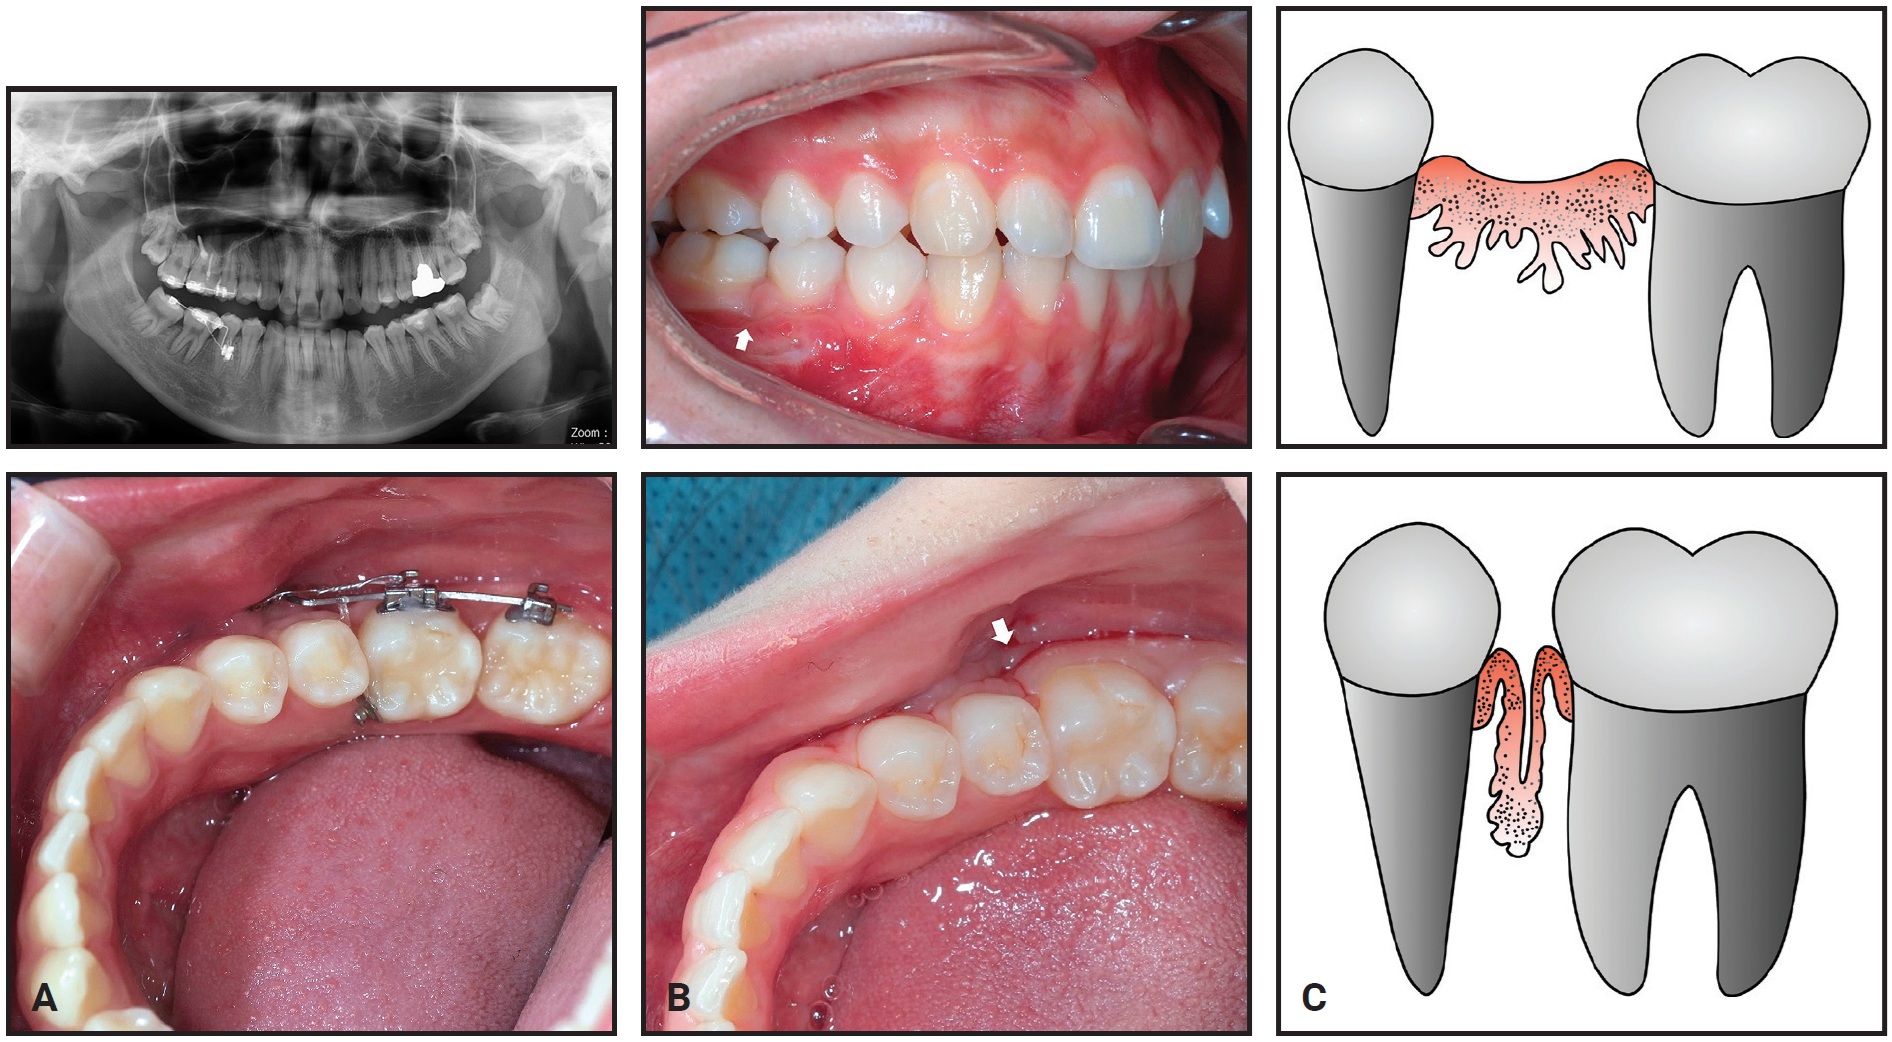

After 20 months of treatment, most of the lower right first-molar space had been closed by the mesial movement of the second molar. A gingival cleft had developed as a result of soft-tissue folding, and bone loss on the mesial side of the lower right second molar was evident on a panoramic radiograph at 24 months (Fig. 10).

Fig. 10 Case 2. A. Gingival cleft caused by soft-tissue folding after 24 months of treatment, with bone loss apparent on mesial side of lower right second molar. B. Gingival cleft evident in interproximal area of second premolar and protracted second molar. C. Illustration of gingival cleft caused by closure of edentulous space.

Total treatment time was 27 months (Fig. 11). The post-treatment records showed the gingival cleft between the second premolar and the protracted second molar, bone resorption in the mesial part of the second molar, and apical root resorption of the protracted second molar. In addition, bone atrophy in the buccolingual dimension was observed in the bone between the second premolar and the second molar.

The overlying soft tissue on the edentulous ridge eventually matures after molar extraction. Because soft tissue remodels more slowly than the bone does, this mature soft tissue may fold down and produce a soft-tissue cleft during space closure (Fig. 10C). In Case 1, the presence of the mesial root prevented soft-tissue maturation and may thus have reduced the risk of developing a soft-tissue cleft. In Case 2, the soft-tissue folding caused bone resorption, which can be accelerated when a patient has poor oral hygiene.14 If a large edentulous space is involved, guided bone regeneration should be considered to prevent such bone resorption.6 A preventive gingival graft or apically repositioned flap can be considered ahead of space closure, or the folded soft tissue can be removed.